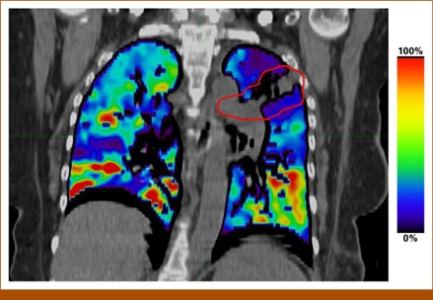

A imagem abaixo diz muito sobre isto e é quase autoexplicativa:

A imagem mostra áreas em vermelho com melhor perfusão e em azul escuro aquelas com maior déficit ventilatório. A linha em vermelho mostra a região do tumor e áreas de baixa ventilação ao redor.

Mapeando o pulmão dessa forma, poderíamos evitar que a composição de campos da radioterapia atravessem áreas de melhor perfusão, minimizando as perdas pulmonares e funcionais futuras. Esse conceito é muito interessante e precisa ser melhor estudado para sua aplicação.